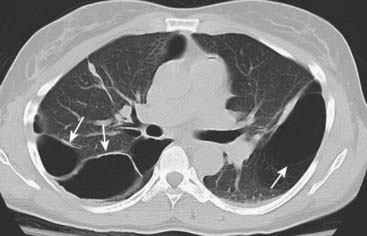

Figure 12-23 Emphysema.

On conventional radiographs, the imaging findings of COPD are hyperinflation, including flattening of the diaphragm, especially on the lateral exposure (solid white arrow in B), increase in the retrosternal clear space (dotted white arrow), hyperlucency of the lungs with fewer than normal vascular markings, and prominence of the pulmonary arteries secondary to pulmonary arterial hypertension (solid white arrows in A).

image On conventional radiographs, the most reliable finding of COPD is hyperinflation, including flattening of the diaphragm, especially on the lateral exposure (Fig. 12-23). Other findings may include an increase in the retrosternal clear space, hyperlucency of the lungs with fewer than normal vascular markings visible, and prominence of the pulmonary arteries from pulmonary arterial hypertension.